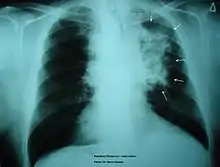

Chronic Obstructive Pulmonary Disease

Smoking is found to be the most important causative factor leading to COPD.[23] Because of the altered inflammatory response of the macrophages, smoking induces inflammation across the entire airway, which in turns obstructs the airflow. Symptoms of COPD include persistent coughing, wheezing, chest infections and breathlessness. Treatments for COPD usually focus on the source of the problem, which is smoking, thus the general treatment is going through smoking rehabilitation which including nicotine replacement therapy, mental therapy for advice, and support to quit smoking. In certain urgent cases, direct constriction also occurs, in which bronchodilators allow the airway to dilate.